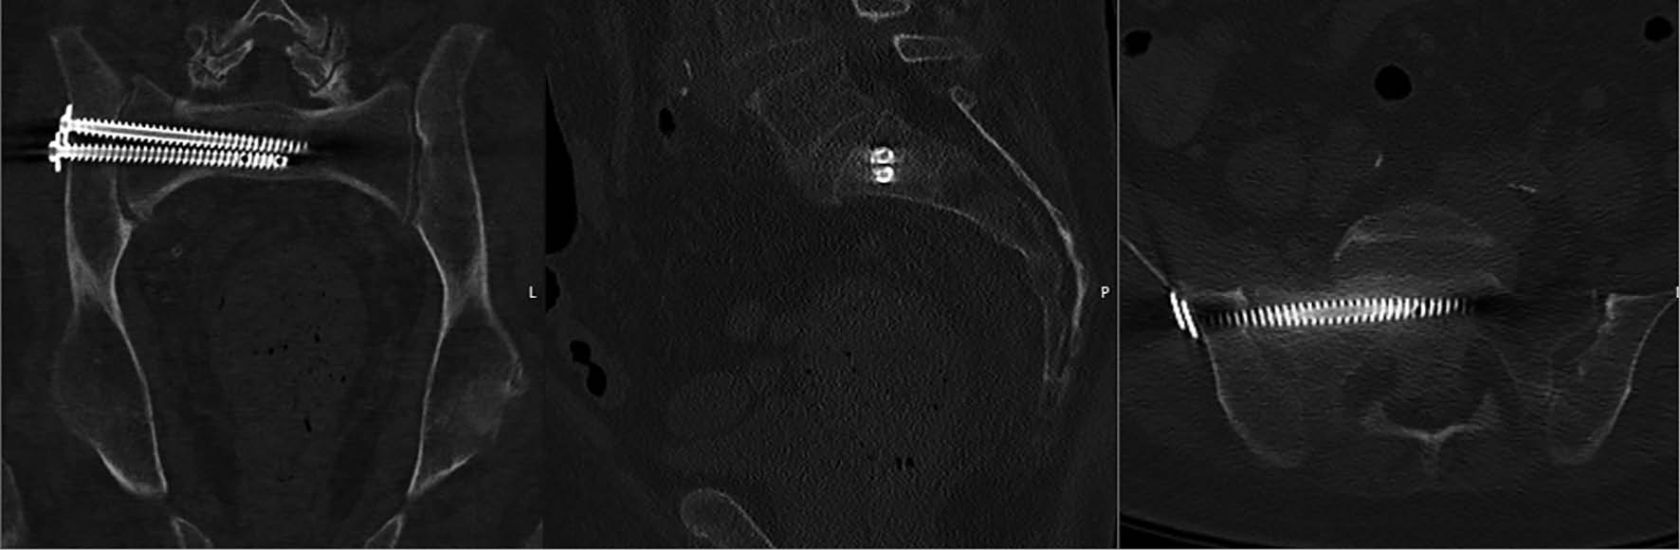

Abb. 1: postoperative CT-Lagekontrolle einer rechtsseitigen Doppelschrauben-osteosynthese einer transforaminalen Os sacrum-Fraktur einschließlich sagitaler und coronarer Rekonstruktion

Transiliosakrale Verschraubungen dienen der minimalinvasiven operativen Versorgung des hinteren Beckenrings. Aufgrund der perkutanen Technik sind Möglichkeiten der Reposition sehr beschränkt. Minimalvorgabe ist die Nutzung eines Bildwandlers in Inlet, Outlet und lateraler Projektion, Implantatfehllagen lassen sich durch navigierte Techniken mittels 3D-Scan weiter minimieren. Das operative Vorgehen kann sowohl in Bauch- als auch in Rückenlage erfolgen. Die Markierung der lokalen Anatomie sowie der sogenannten „safe zone“ des Os sacrum auf der Haut haben sich bewährt. Über Stichinzisionen werden 1 oder 2 K-Führungs-Drähte in den S1 bzw. jeweils 1 Draht in S1 sowie S2 über die laterale Iliumcorticalis, die Iliosakralfuge, die Massa lateralis bis in den Korpus S1 bzw. S1/S2 vor- und folgend überbohrt [10]. Da in der Regel keine „open-book“-Instabilität vorliegt, werden anschließend Vollgewindeschrauben (6,5 – 7,5 mm mit Unterlegscheibe) eingeschraubt. Diese werden heute von nahezu allen Firmen mit Perforationen an der Schraubenspitze hergestellt, um, ebenso minimalinvasiv und falls gewünscht, eine zusätzliche Augmentation der Schrauben mit Zement zu ermöglichen. Biomechanische Studien konnten zeigen, dass 2 ipsilaterale Schrauben S1 [Abb. 1] bzw. je 1 in S1 und S2 eine deutlich erhöhte Stabilität gegenüber einer singulären Schraube erreichen [11], hier insbesondere eine erhöhte Rotationsinstabilität gegenüber nur einer S1-Schraube [12].

Abb. 2: Coronare CT-Kontrolle nach Versorgung einer bilateralen mehrzeitig entstandenen Insuffizienzfraktur mittels Transiliosacralem Bar.

Hierunter werden Osteosynthesetechniken verstanden, die am lateralen Ilium einerseits das gesamte Sacrum querend und das Ilium der Gegenseite ebenso perforierend, so dass im Anschluss beide Iliumblätter mit dem gesamten Sacrum in der Regel in Höhe S1 verblockt sind [Abb. 2]. In dieser Form dienen sie der bds. iliosacralen Stabilisierung, zeigen jedoch gegenüber einer bilateralen Verschraubung in einer biomechanischen Arbeit Stabilitätsvorteile [12].